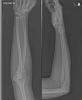

Elleboog